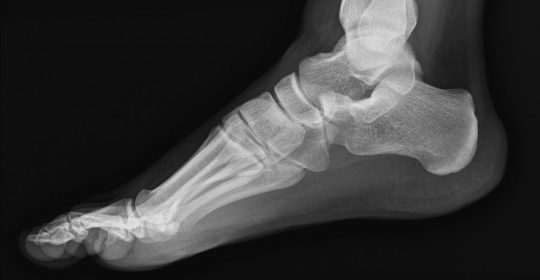

Para llevar a cabo este proceso, el software identifica de manera exacta las heridas a partir de imágenes obtenidas mediante TAC. Esta prueba diagnóstica de rayos X permite observar el interior del organismo en forma de cortes transversales o tridimensionales, lo que permite conocer de forma precisa si se observan solo partes óseas o también hay músculos, tendones u otro tipo de tejidos blandos que no se diferencian en una radiografía convencional.

Gracias a estas imágenes y al algoritmo desarrollado por los investigadores, se muestra el número de piezas, la orientación y separación de las mismas, y se marcan las zonas de contacto entre ellas, incluso si la imagen aparece rotada. El sistema completo podría compararse con la marca por separado de cada parte de un puzle para conocer previamente cómo recomponer la totalidad.